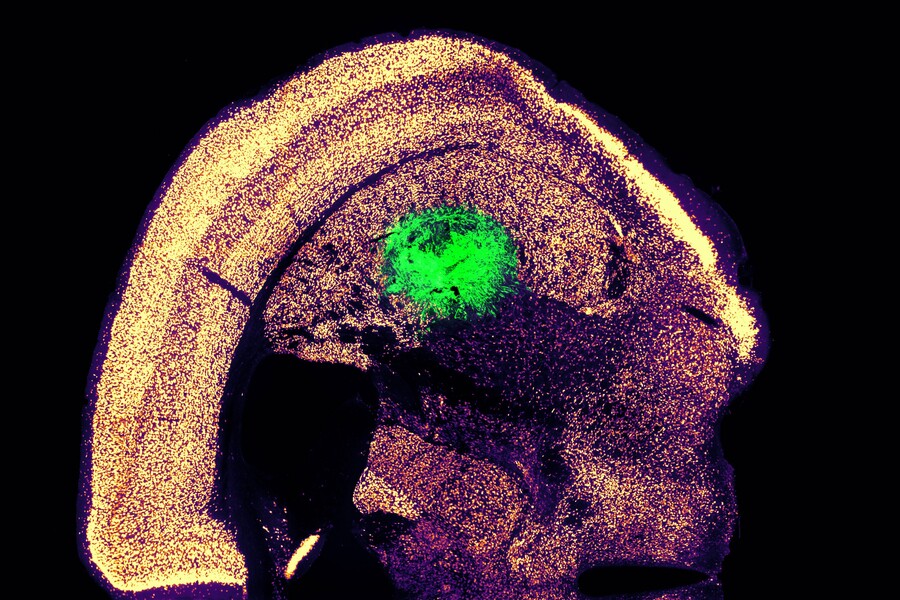

MIT

The team tested the technique by converting mouse skin cells to motor neurons. And sure enough, this resulted in a yield of over 1,000%. The resulting motor neurons were found to produce detectable electrical activity and calcium signaling, indicating they were functional. In follow-up tests, the neurons were grafted into the brains of living mice, where they seemed to form connections with other brain cells.